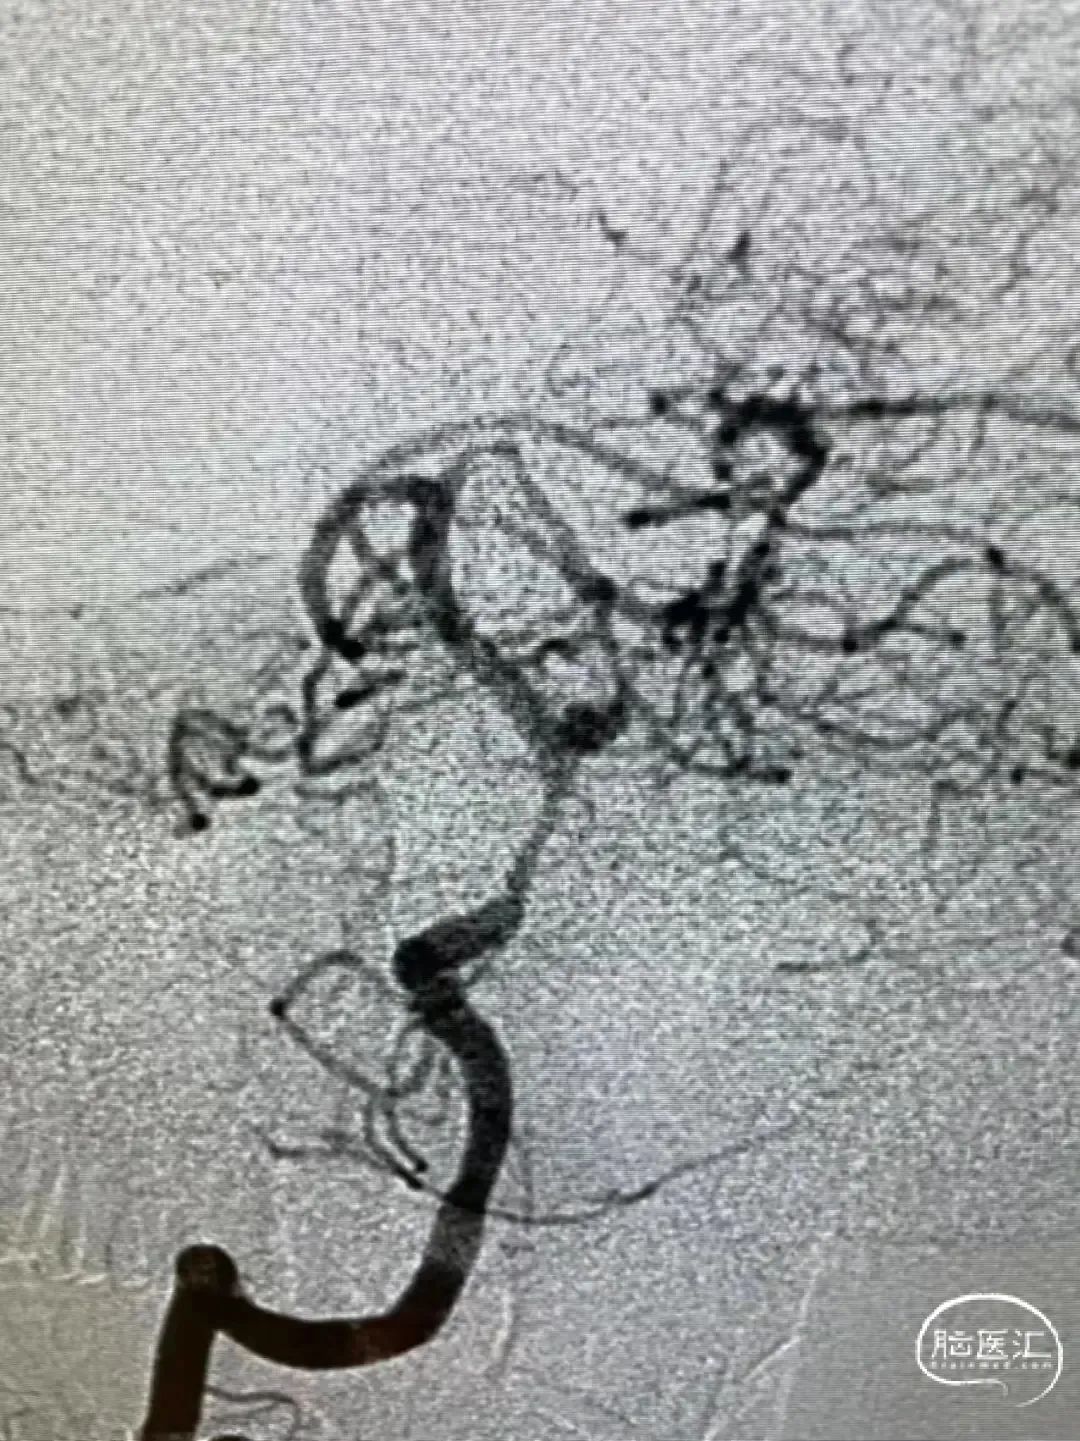

术后即刻影像

栓塞过程及术后影像